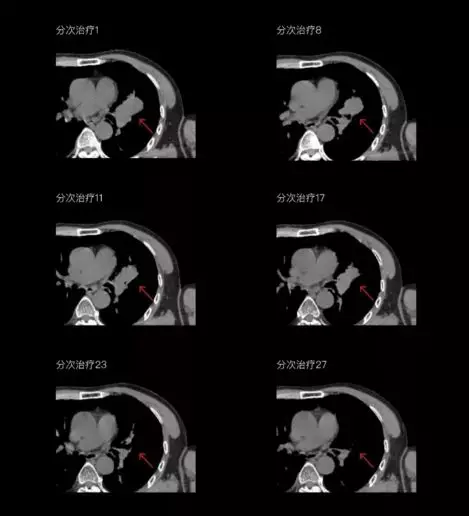

一體化CT-linac讓自適應放療ART概念變?yōu)楝F(xiàn)實?;颊呷煶虪顟B(tài)監(jiān)控,適時在線調整治療計劃,精準控制治療劑量,為患者動態(tài)定制個體化治療方案。uAI賦能智能勾畫和自動計劃,秒級勾勒靶區(qū)和危及器官,大幅縮短自適應放療時間。

聯(lián)影CT-linac全程監(jiān)測治療過程病灶的變化,及時調整和優(yōu)化治療方案